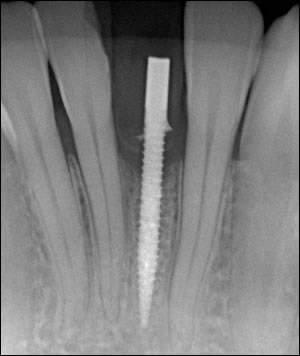

Fig 2: The Mini Dental Implant in place.